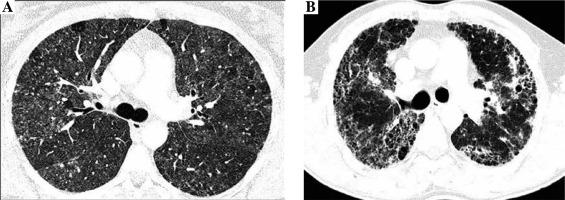

Radiologists evaluated the presence and intensity of typical HP features in CT images, including centrilobular nodules, diffuse ground glass opacifications, air trapping, and mosaic attenuation, and features of lung fibrosis, such as reticulation, traction bronchiectasis, and honeycombing. Lung fibrosis on CT images was staged as: 0. No fibrosis (Fig. 1A), 1. Areas of reticulation with traction bronchiectasis, 2. Advanced lung fibrosis with honeycombing and bronchocentric fibrosis (Fig. 1B). Characteristics of study population is presented in Table 1.

Fig. 1

Non-fibrosing and fibrosing hypersensitivity pneumonitis. Figures present CT axial images of the lung window. A) Bilateral patchy ground-glass opacities, diffuse, poorly defined centrilobular nodules, focal regions of decreased attenuation corresponding to air trapping lobules and normal lungs, characteristic for HP mosaic attenuation, and no features of lung fibrosis (stage 0). B) Fibrosing hypersensitivity pneumonitis – patchy ground-glass opacities and diffuse reticulation with traction bronchiectasis and focal honeycombing, which are the features of advanced lung fibrosis (stage 2)